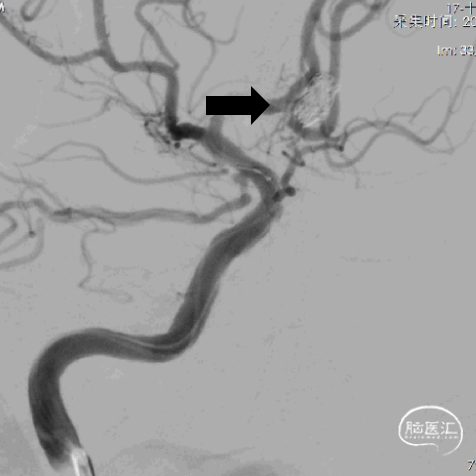

5、双微导管分区填塞动脉瘤。

6、填圈期间动态造影监测左侧大脑前动脉血流有无影响。

7、在瘤颈处可见可疑血栓影。

8、左侧大脑前动脉血流变慢。

9、动脉给予替罗非班后,左侧大脑前动脉血流未见好转。

10、将瘤颈口的微导管撤出后,左侧大脑前动脉血流较前略有好转。

11、反复造影观察后血流速度仍然减慢,造影见少量弹簧圈突入前交通动脉。